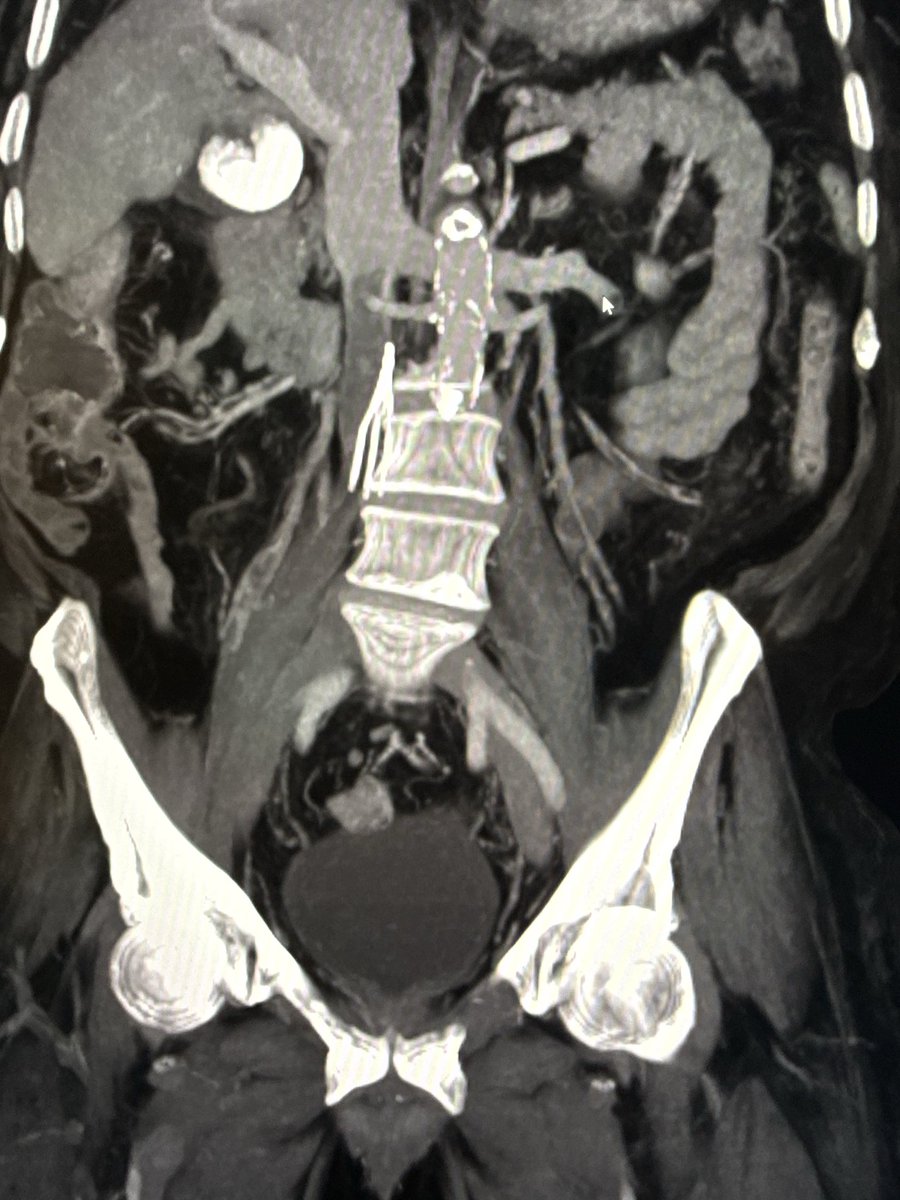

Sometimes controlled extravasation is beneficial. T10 and recurrent T9 fracture s/p T8,9 kypho previously. Fracture morphology complicated by DISH. Transpedicular disc access for T9 kypho and discoplasty to consolidate osteophyte and endplate. Ugly, but effective. #disasterplasty

Curved needles and cement cannulas are helpful for targeting focal fracture clefts. Small T8 superior endplate cleft after otherwise sufficient kypho at OSH was not amenable to pedicular access. Transdiscal access from above made for an easy fix.

(4/4) A bit more cement and done. The main principle for treatment of hinge-fractures (DISH, ank spond) is stabilization, primarily from compressive forces. Cement from top of T9 to bottom of T10 accomplishes this. Close follow-up to ensure stability and tx add'l fractures.

(3/) After initial cement from these accesses, the air filled fracture clefts are filled, but right side T10 is bare. Osteophyte blob = 👍🏼 Old accesses removed, new right transpedicular access with standard craniocaudal angulation. Moar curette. Curette = 🐐